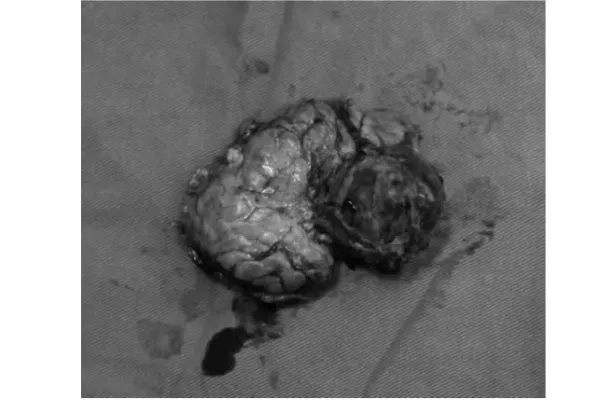

最终,陈艳军主任团队以极致细致、极致轻柔、极致保功能的手术态度,圆满完成了腹腔镜保脾胰体尾切除术(Kimura术式)。术中出血仅40ml,不仅完整切除肿瘤,更完美保留了脾脏及其血供、保留了大部分胰腺功能,实现了真正意义上的保器官、保功能、保未来。